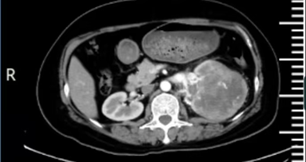

近日,我院泌尿外科在学科带头人陈善群主任的带领下,成功为一位 56 岁的女性患者施行了后腹腔镜下左肾癌根治性切除手术。此次手术的成功,解除了恶性肿瘤对患者生命的严重威胁,充分展现出泌尿外科在重大疾病诊疗以及高难度手术方面的诊疗能力。

1、病情诊断:

腰部胀痛半月 查出肾脏肿瘤